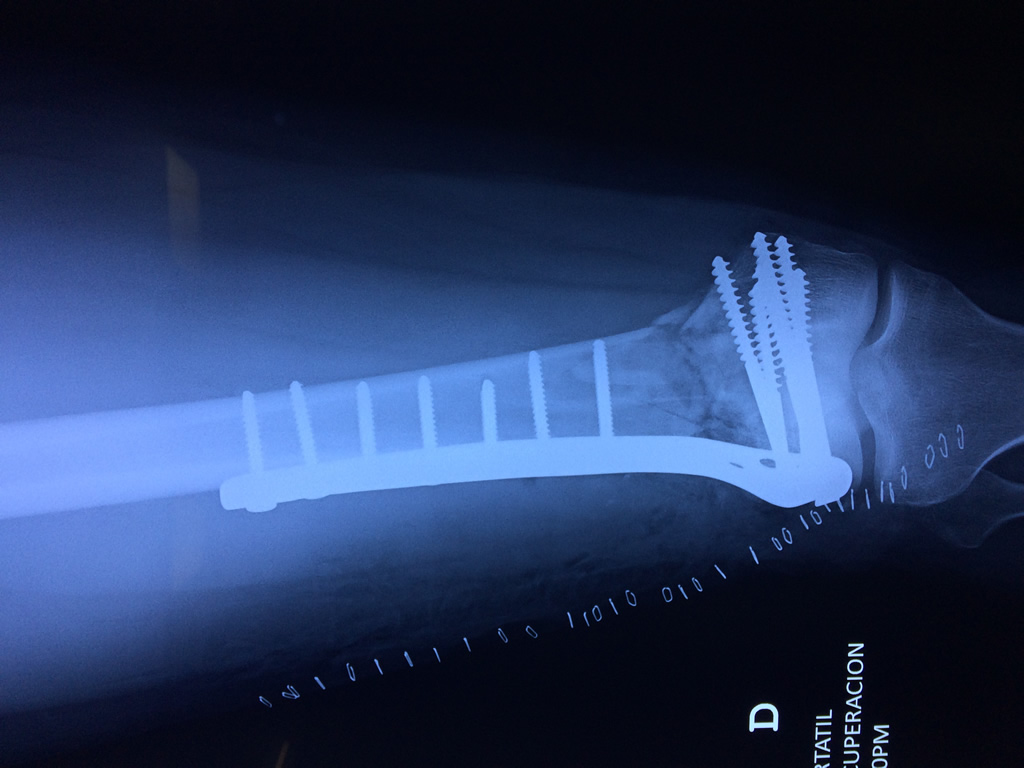

Cirugías de Codo - Fémur

El fémur es el hueso del muslo, el segundo segmento del miembro inferior. Es el hueso más largo, fuerte y voluminoso del cuerpo humano.